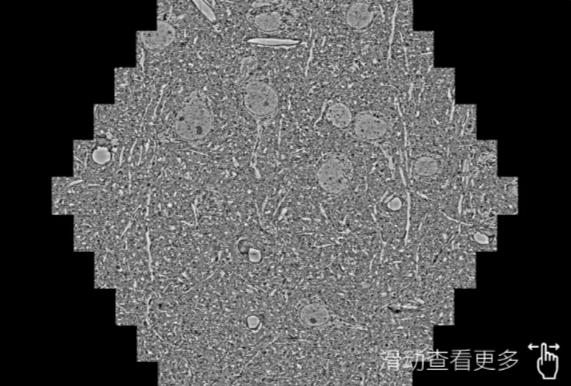

鼠脑切片。左图使用宁德蔡司宁德扫描电镜MultiSEM706对165μmx143pm面积区域成像,耗时仅需1.5秒。右图为鼠脑切片中30μm区域放大效果。样品由芝加哥大学B.Kasthuri提供。